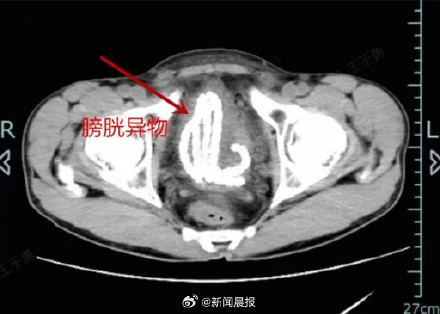

胡先生这才慌了神,赶紧来到医院就诊。接诊的泌尿外科主任医师邓刚得知经过后,感觉到病情不简单,立即为胡先生安排了CT检查,影像结果显示这串玉珠已经由尿道滑进了膀胱,犹如一条“小蛇”盘旋着,绕了好几个弯。

“膀胱异物没有办法自行排出,异物在膀胱的时间越久问题越大,建议尽快手术取出。”泌尿外科主治医师邵佳强调,人的尿道是连接膀胱和外界的通道,尿道口有括约肌,可以控制尿液进出,当有异物“强行”进入尿道口时,括约肌就会受到刺激,强烈收缩,这时候异物就容易被“吸进去”。